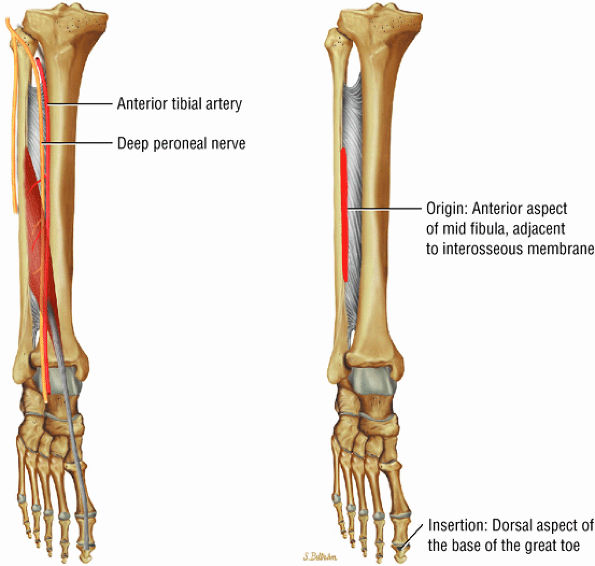

The anterior muscles of the leg are the tibialis anterior (Fig. 5.2), the extensor hallucis longus (Fig. 5.3), the extensor digitorum longus (Fig. 5.4) and the peroneus tertius (Fig. 5.5).

FIGURE 5.2 ● TIBIALIS ANTERIOR The tibialis anterior muscle functions eccentrically after the heel strike to control deceleration of the foot and concentrically after the toe-off in ankle dorsiflexion. In runners and hikers, paratenonitis is associated with the use of excessive eccentric contraction during midfoot and forefoot impact on downhill slopes. Paratenonitis is also associated with direct mechanical irritation from ski boots or hockey skates. The tibialis anterior dorsiflexes and inverts the foot.